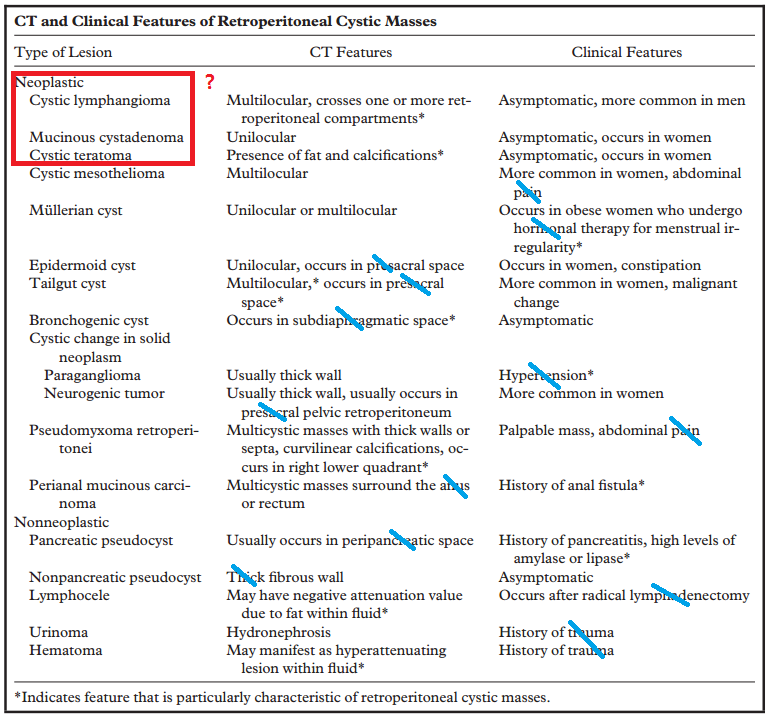

후복강 낭성 종양에는 다음과 같은 것들이 있고 CT 특징을 통한 진단적 접근을 계획하였다.

ddx; lymphangioma, cystic change of neurogenic tumor, cystic lymphadenopathy

; r/o lymphangioma, neurogenic tumor with cystic change, mucinous cystadenoma

조직결과; 혈종

hematoma 예시